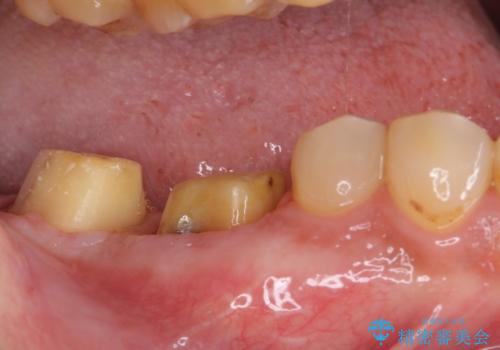

- 親知らずを抜くことが怖く、先送りにした結果親知らずの前の歯に大きな虫歯ができてしまったとのことで来院された患者様です。

親知らずは速やかに抜歯し、手前の歯とその前の歯に歯槽骨にまで及んだ虫歯が認められたため、歯槽骨を削るなどの歯周外科処置を行うこととしました。